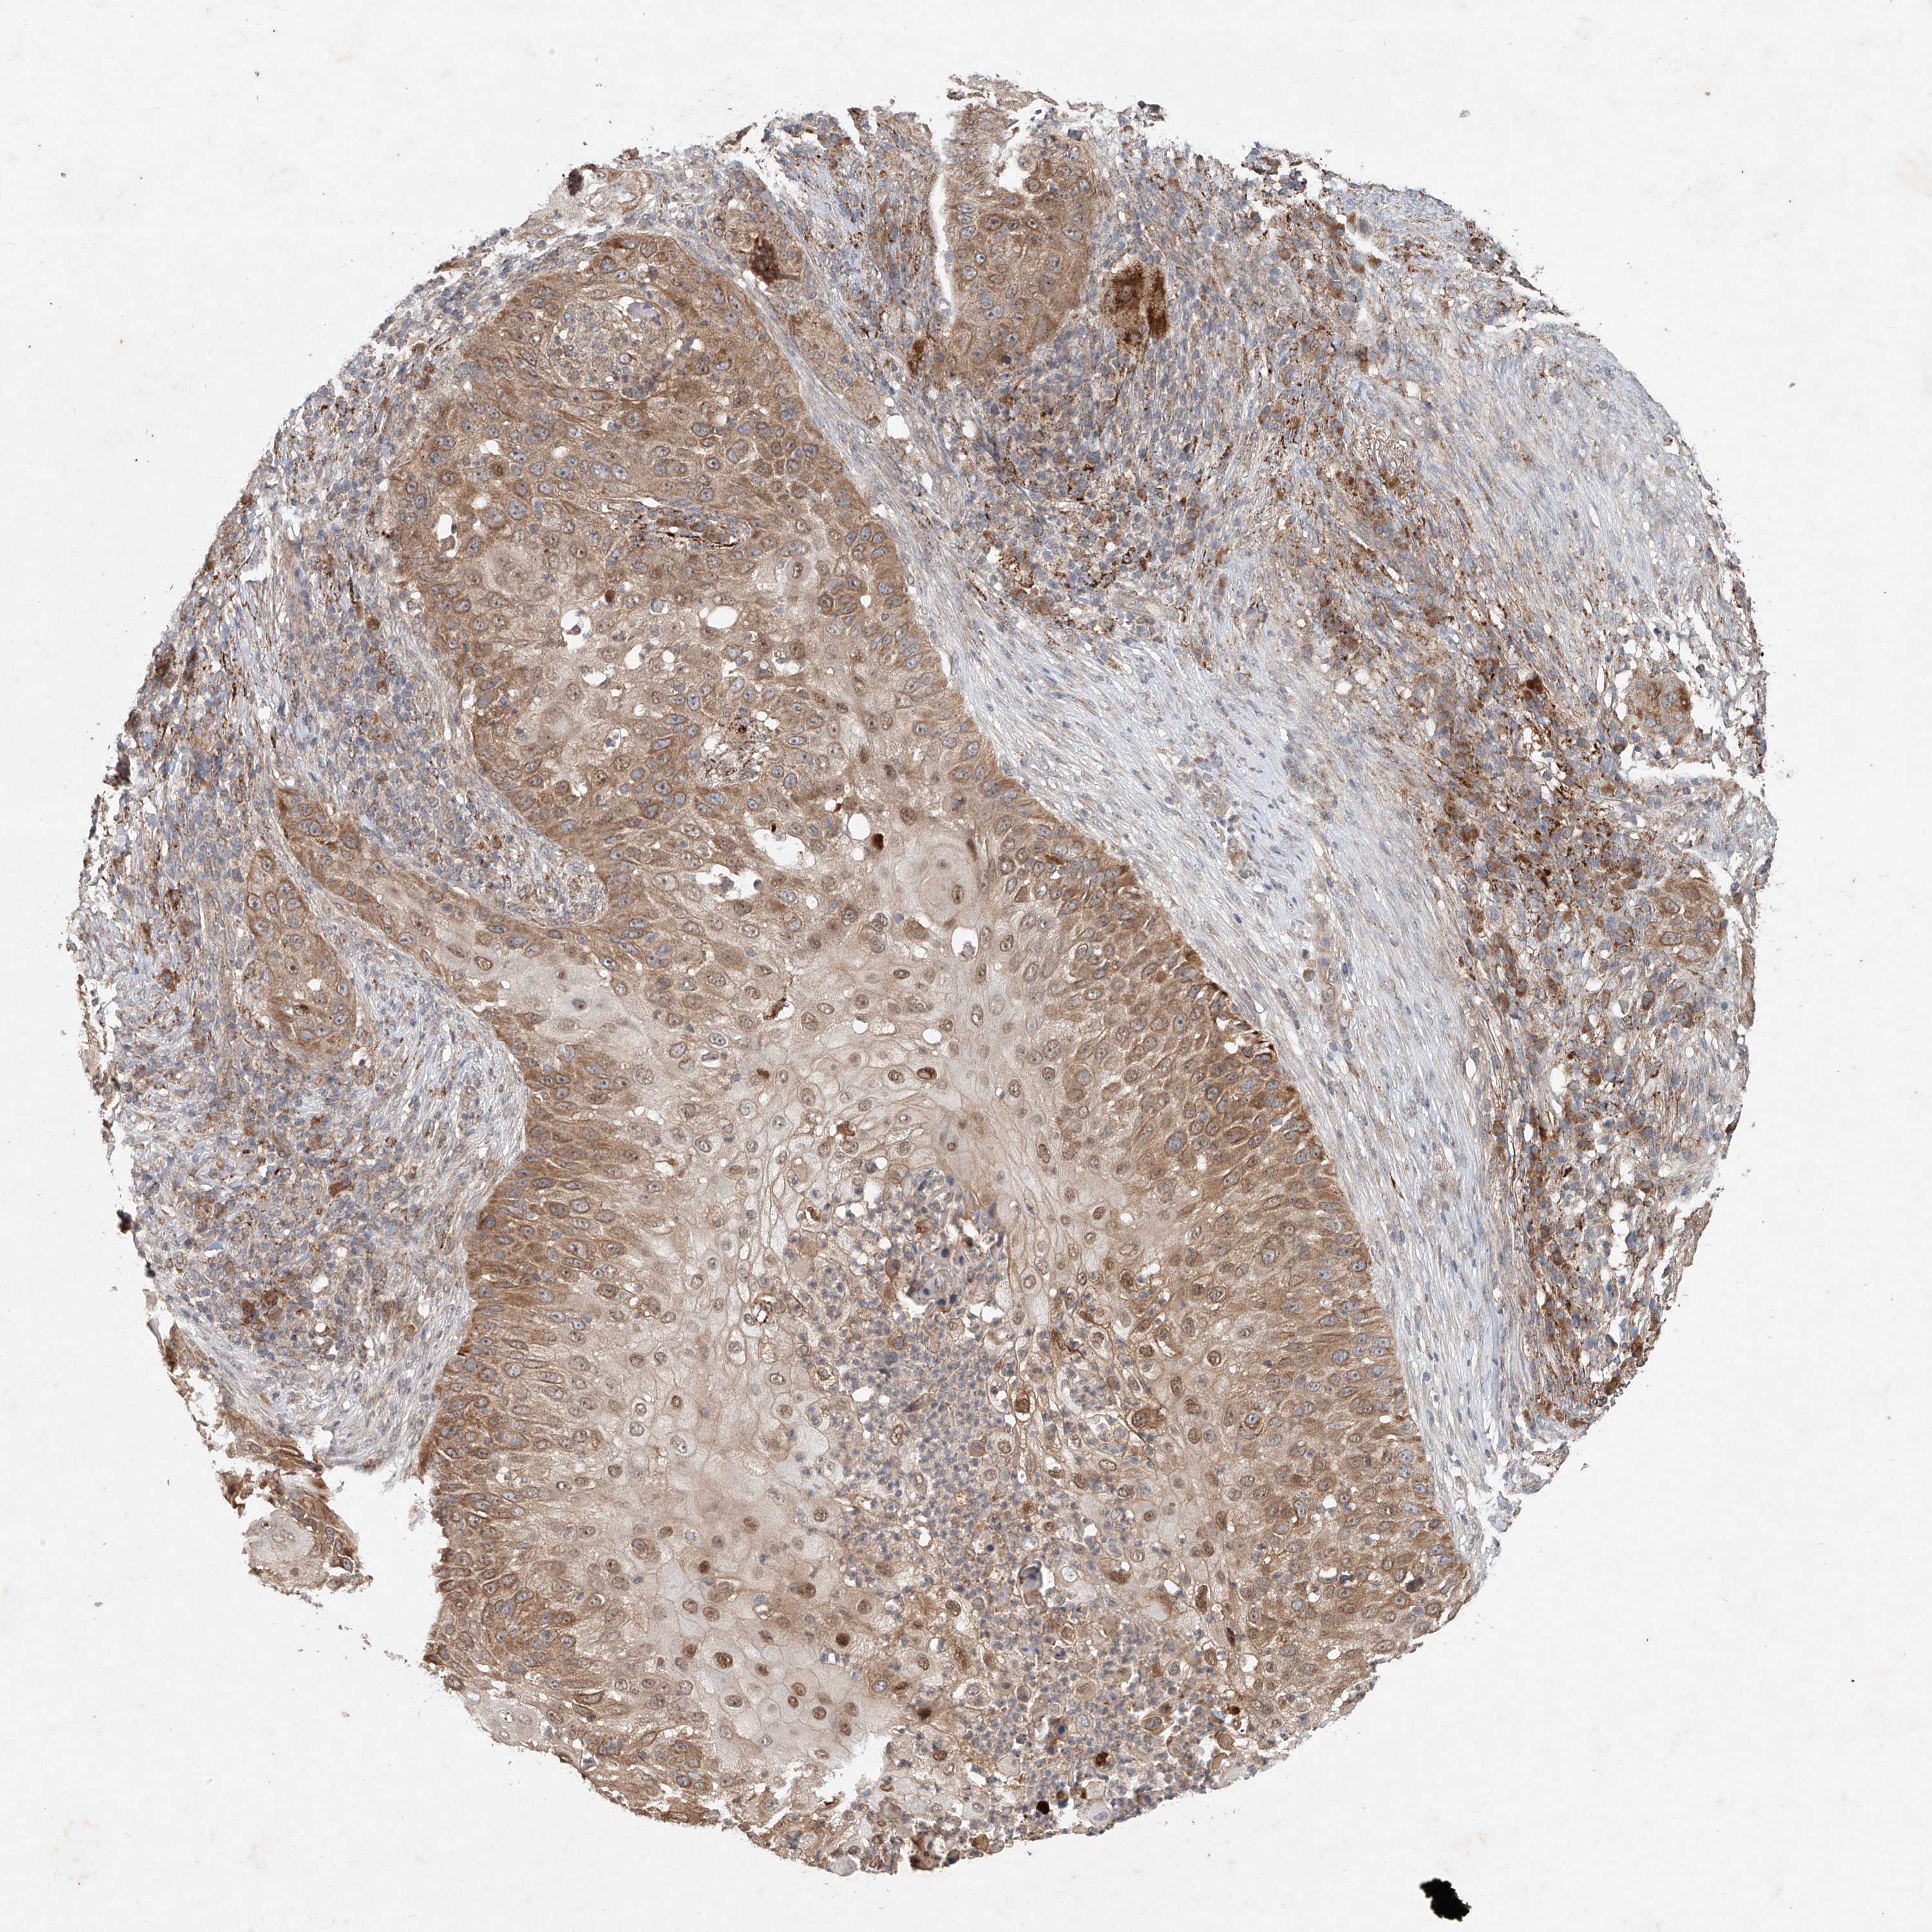

Basal cell and squamous cell cancer

SKIN CANCER - Protein expressioni

A mouse-over function shows sample information and annotation data. Click on an image to view it in a full screen mode. Samples can be filtered based on level of antibody staining by selecting one or several of the following categories: high, medium, low and not detected. The assay and annotation is described here.

Antibody stainingi

Antibody staining in the annotated cell types in the current human tissue is reported as not detected, low, medium, or high, based on conventional immunohistochemistry profiling in selected tissues. This score is based on the combination of the staining intensity and fraction of stained cells.

Each image is clickable and will lead to virtual microscopy that enables deeper exploration of all samples and also displays staining intensity scores, fraction scores and subcellular localization as well as patient and tissue information for each sample.

Antibody HPA029894

Staining

Low

Intensity

Weak

Quantity

<25%

Location

Cytoplasmic/membranous,nuclear

Squamous cell carcinoma, metastatic, NOS

Squamous cell carcinoma, NOS